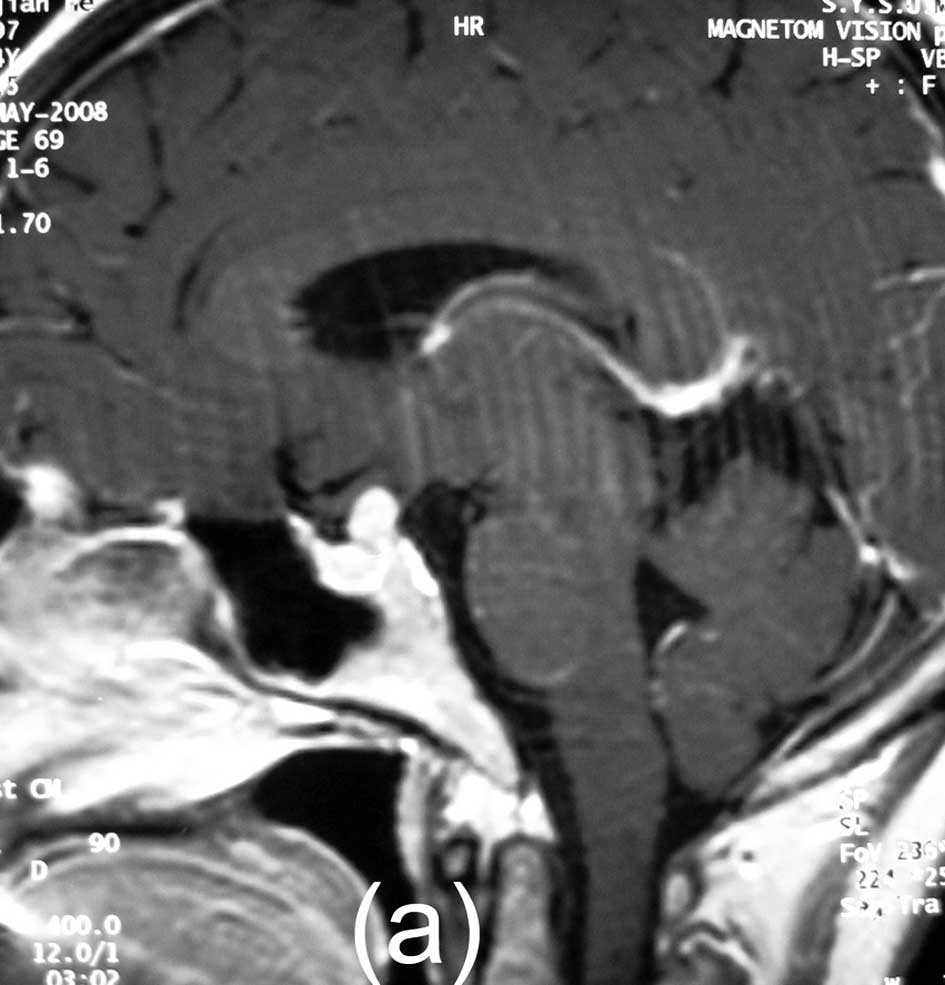

Медицинские исследования: визуальные аспекты болезни Симмондса